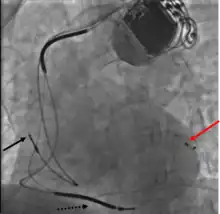

Permanent transvenous pacing

Permanent pacing with an implantable pacemaker involves transvenous placement of one or more pacing electrodes within a chamber, or chambers, of the heart, while the pacemaker is implanted under the skin below the clavicle. The procedure is performed by incision of a suitable vein into which the electrode lead is inserted and passed along the vein, through the valve of the heart, until positioned in the chamber. The procedure is facilitated by fluoroscopy which enables the physician to view the passage of the electrode lead. After satisfactory lodgement of the electrode is confirmed, the opposite end of the electrode lead is connected to the pacemaker generator.

A pacemaker may be implanted whilst a person is awake using local anesthetic to numb the skin with or without sedation, or asleep using a general anesthetic.[25] An antibiotic is usually given to reduce the risk of infection.[25] Pacemakers are generally implanted in the front of the chest in the region of the left or right shoulder. The skin is prepared by clipping or shaving any hair over the implant site before cleaning the skin with a disinfectant such as chlorhexidine. An incision is made below the collar bone and a space or pocket is created under the skin to house the pacemaker generator. This pocket is usually created just above the pectoralis major muscle (prepectoral), but in some cases the device may be inserted beneath the muscle (submuscular).[26] The lead or leads are fed into the heart through a large vein guided by X-ray imaging (fluoroscopy). The tips of the leads may be positioned within the right ventricle, the right atrium, or the coronary sinus, depending on the type of pacemaker required.[25] Surgery is typically completed within 30 to 90 minutes. Following implantation, the surgical wound should be kept clean and dry until it has healed. Some movements of the shoulder within a few weeks of insertion carry a risk of dislodging the pacemaker leads.[25]